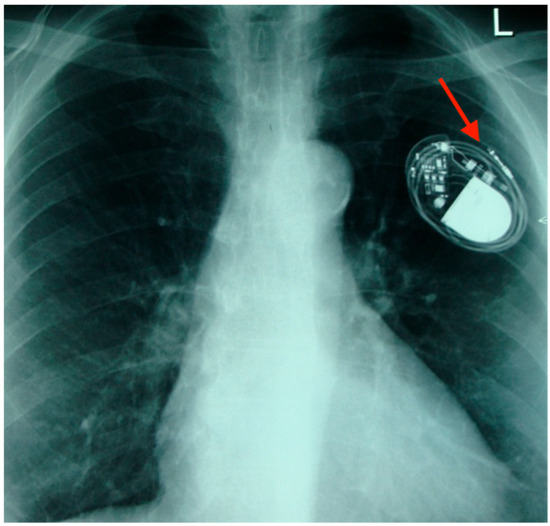

We present the case of a 27-year-old woman diagnosed with Löffler’s endomyocarditis complicated by intraventricular thrombus and cerebral infarction. She was treated with prednisolone and anticoagulation therapy; however, tapering of corticosteroids resulted in recurrence of intraventricular thrombosis. Given disease relapse after medication withdrawal,

We present the case of a 27-year-old woman diagnosed with Löffler’s endomyocarditis complicated by intraventricular thrombus and cerebral infarction. She was treated with prednisolone and anticoagulation therapy; however, tapering of corticosteroids resulted in recurrence of intraventricular thrombosis. Given disease relapse after medication withdrawal, lifelong anticoagulation was indicated. At 29 years of age, she sought pregnancy counseling. Conception was permitted after stabilization of prednisolone dosage, with a planned switch from a vitamin K antagonist to therapeutic-dose unfractionated heparin during pregnancy. Following disease stabilization, she conceived via artificial insemination. Serial echocardiography at 22 and 34 weeks of gestation demonstrated preserved cardiac function without thrombus recurrence. She delivered a healthy infant by emergency cesarean section at 39 weeks of gestation due to fetal distress. No thrombus recurrence was observed postpartum, and she remained clinically stable during 13 months of follow-up. This represents the case of a successful pregnancy in a woman with a history of recurrent intraventricular thrombosis due to Löffler’s endomyocarditis, highlighting the importance of early diagnosis, sustained immunosuppression, individualized anticoagulation, and multidisciplinary preconception planning.

Figure 1